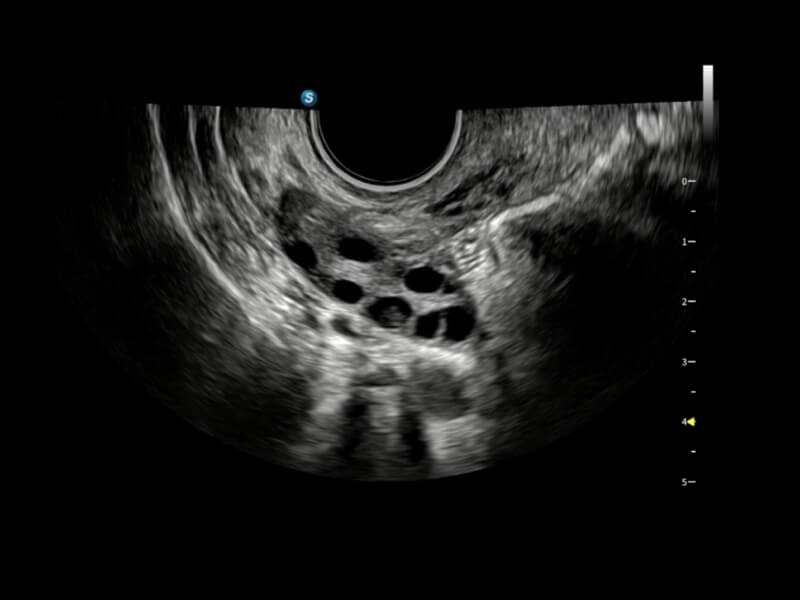

• Hohe Effizienz in der Follikelanalyse wird durch AVC Follicle erreicht: Die Follikel werden in den Ergebnissen nach Größe sortiert und zur intuitiven Visualisierung in verschiedenen Farben dargestellt.